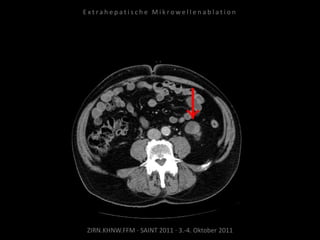

Erneute Ablation der Metastase

kaudal der linken Niere am

09.05.2011:

2 Nadelpositionen.

Verlaufskontrolle:

MRT 09.06.2011

MRT 10.08.2011

CT 15.08.2011

Keine weitere Tumorvitalität.